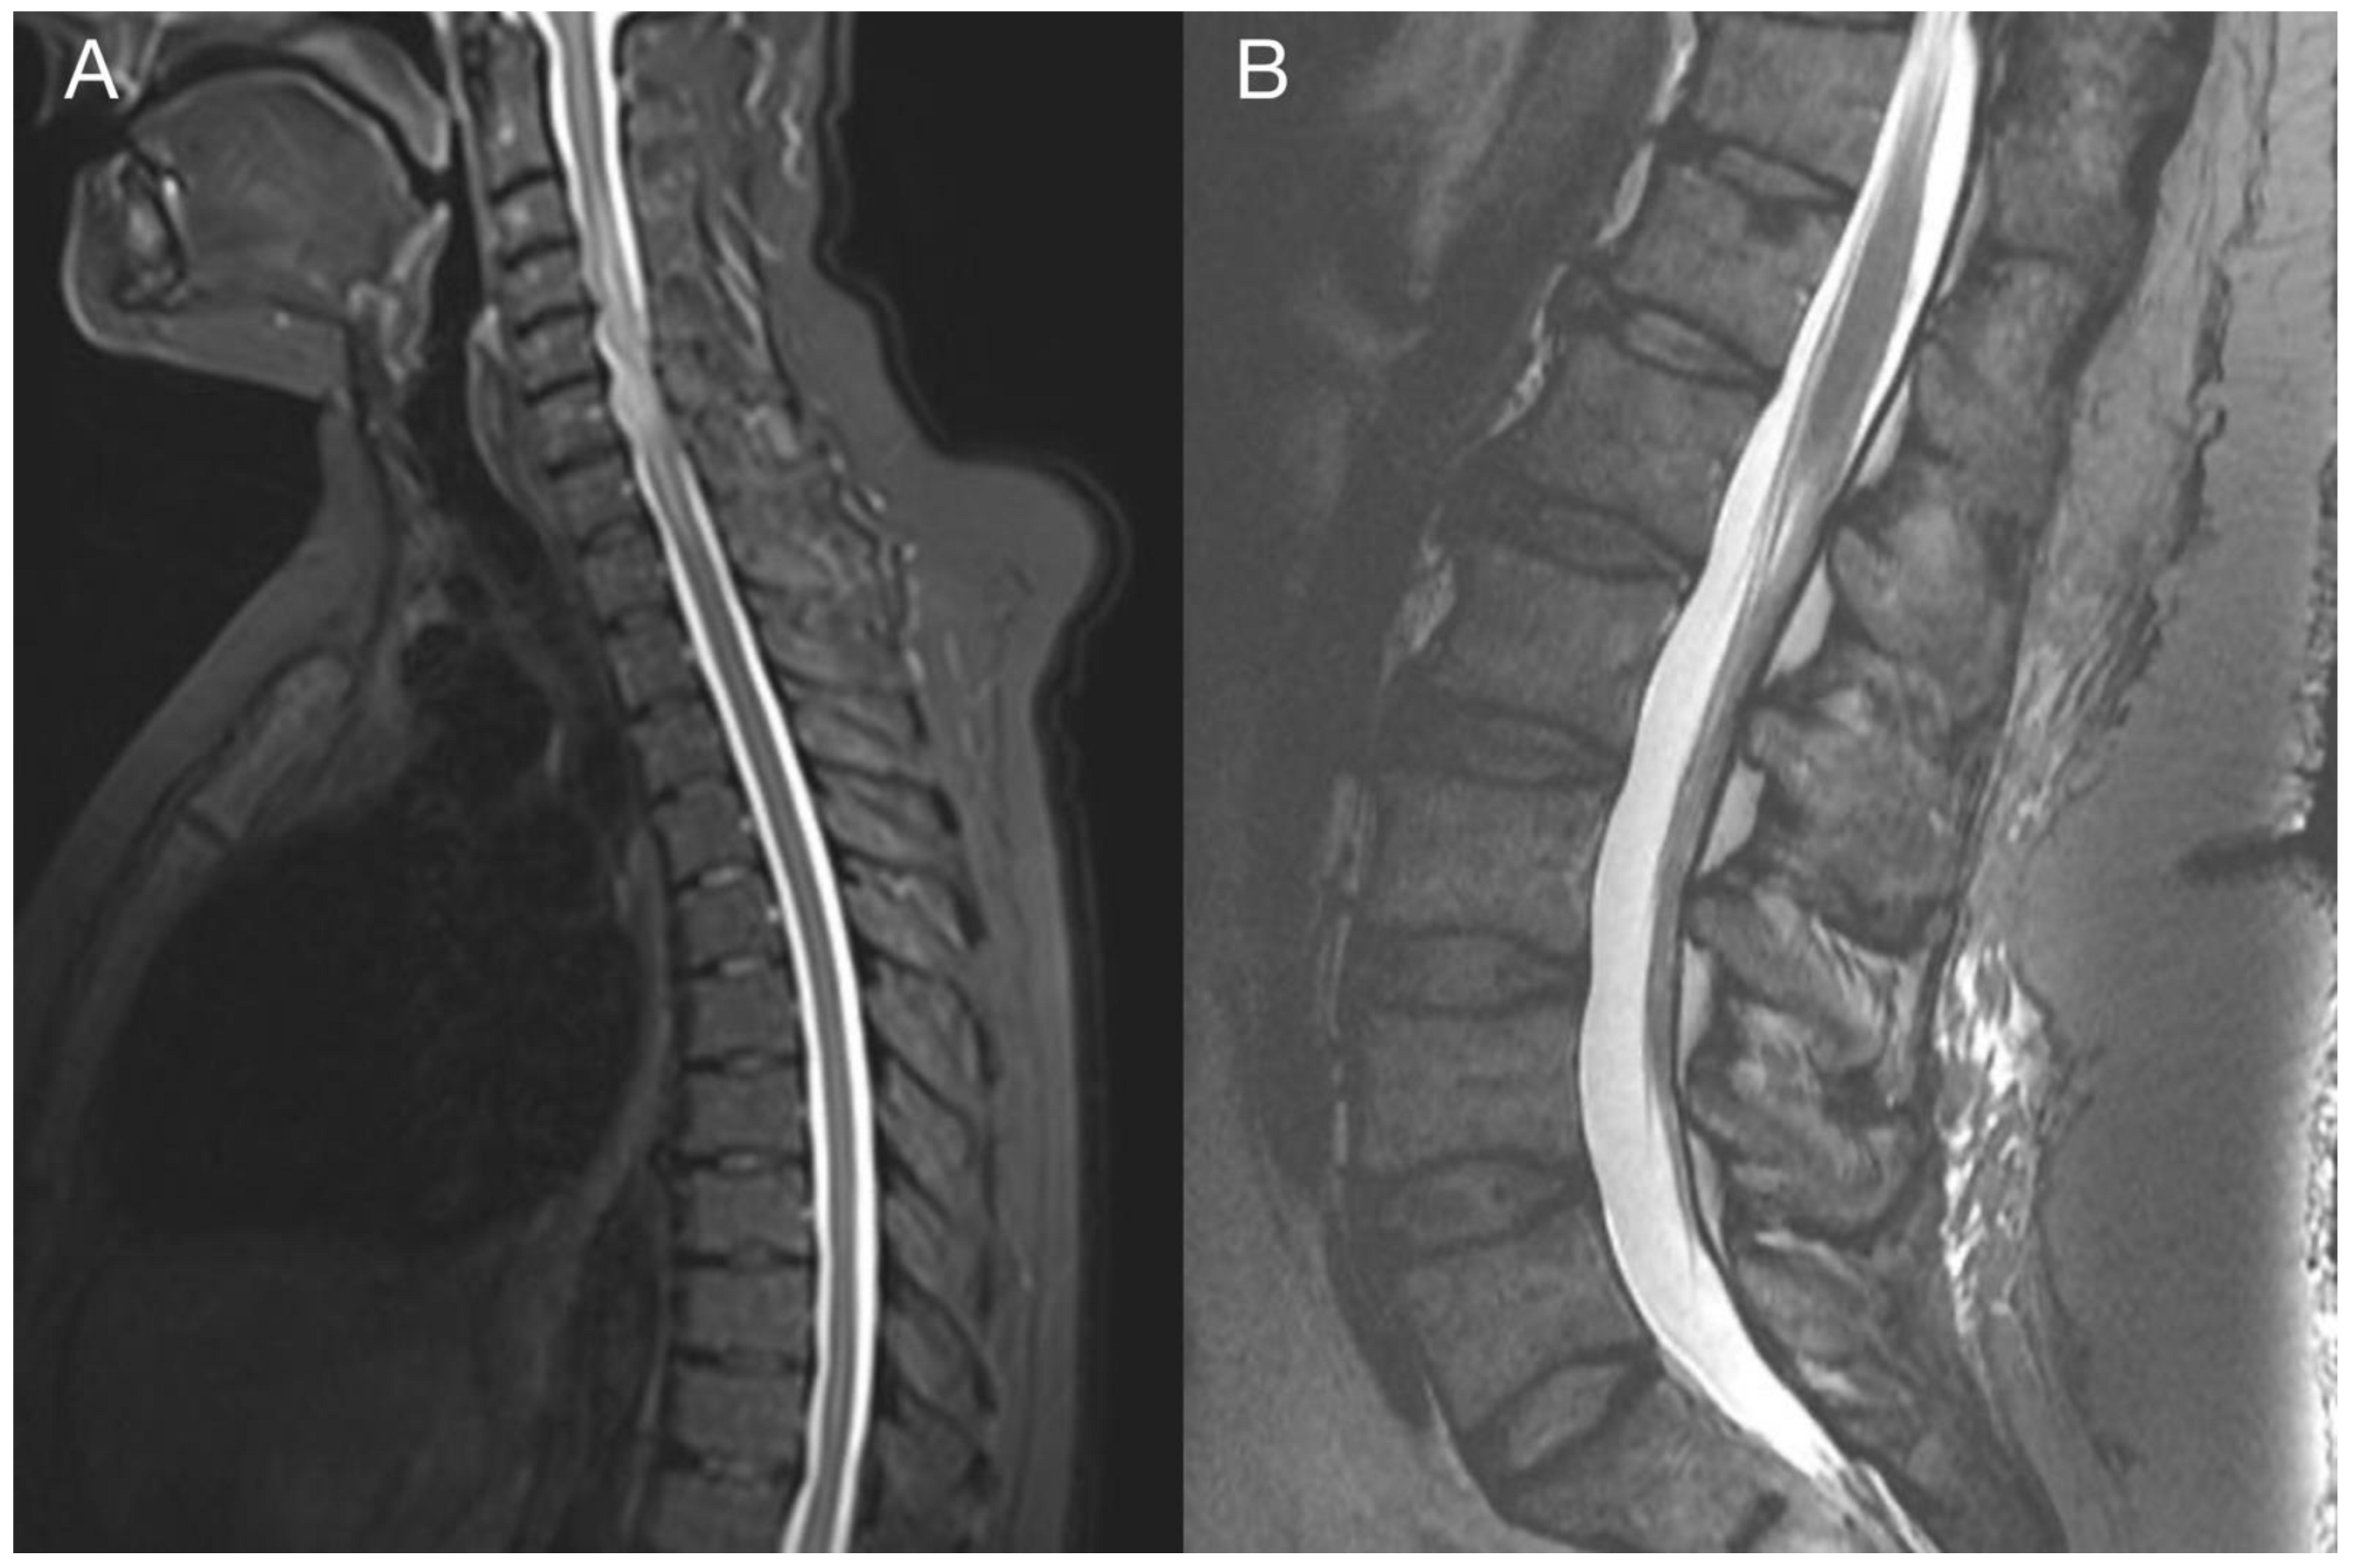

2. Case Report